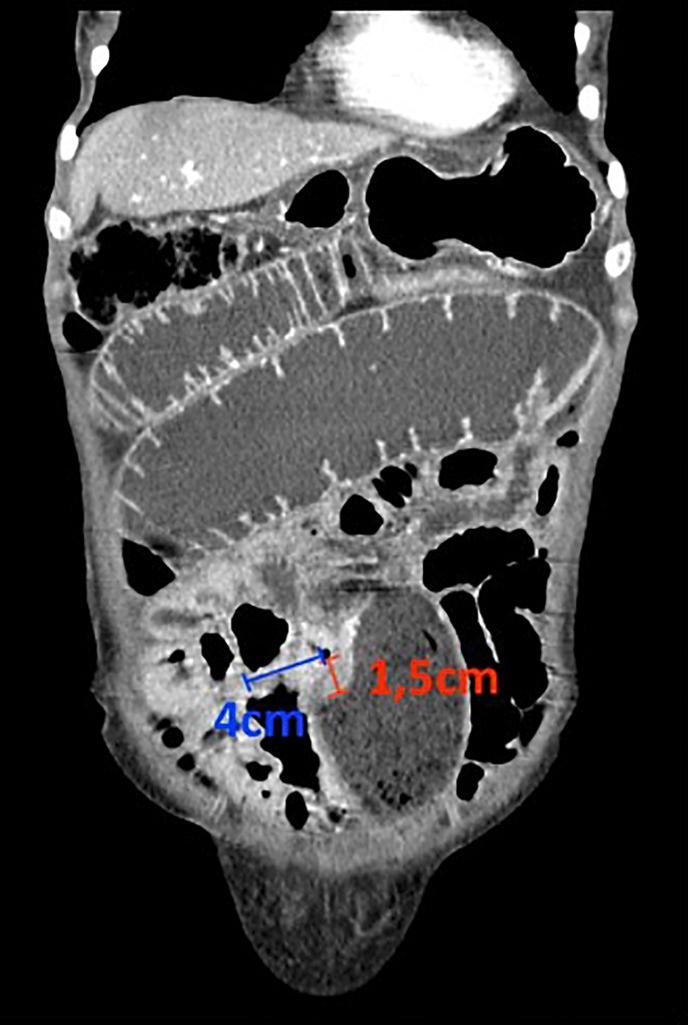

CASE PRESENTATION

We report a case of a female patient with celiac disease with poor adherence to a gluten-free diet who presented with small bowel obstruction due to a primary ileal adenocarcinoma. The patient remains asymptomatic, adherent to the gluten-free diet, and without clinical, biochemical, or imaging evidence of cancer recurrence.